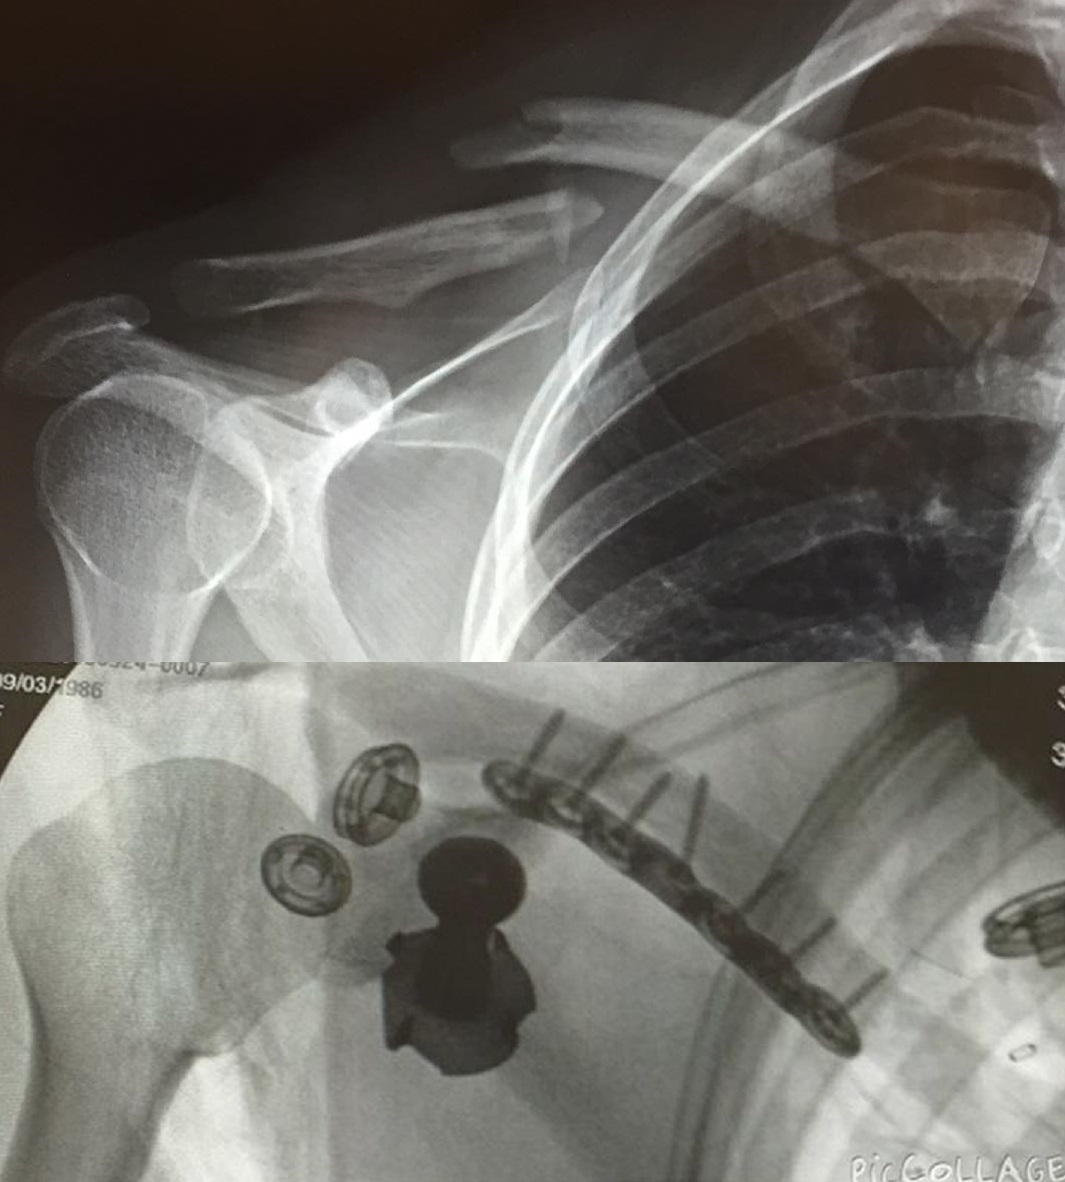

[14 / 3 / 12] 2MiB, 240x180, nashquad.gif View SameGoogleImgOpsiqdbSauceNAO Thread Reply Original Report Media View Same Google ImgOps iqdb SauceNAO Download Horrifying wrestling injuries Anonymous Sat 25 Mar 2023 19:46:53 No.9467271 View ViewReplyOriginalReport Quoted By: >>9467291 >>9467293 >>9467811 >>9468966